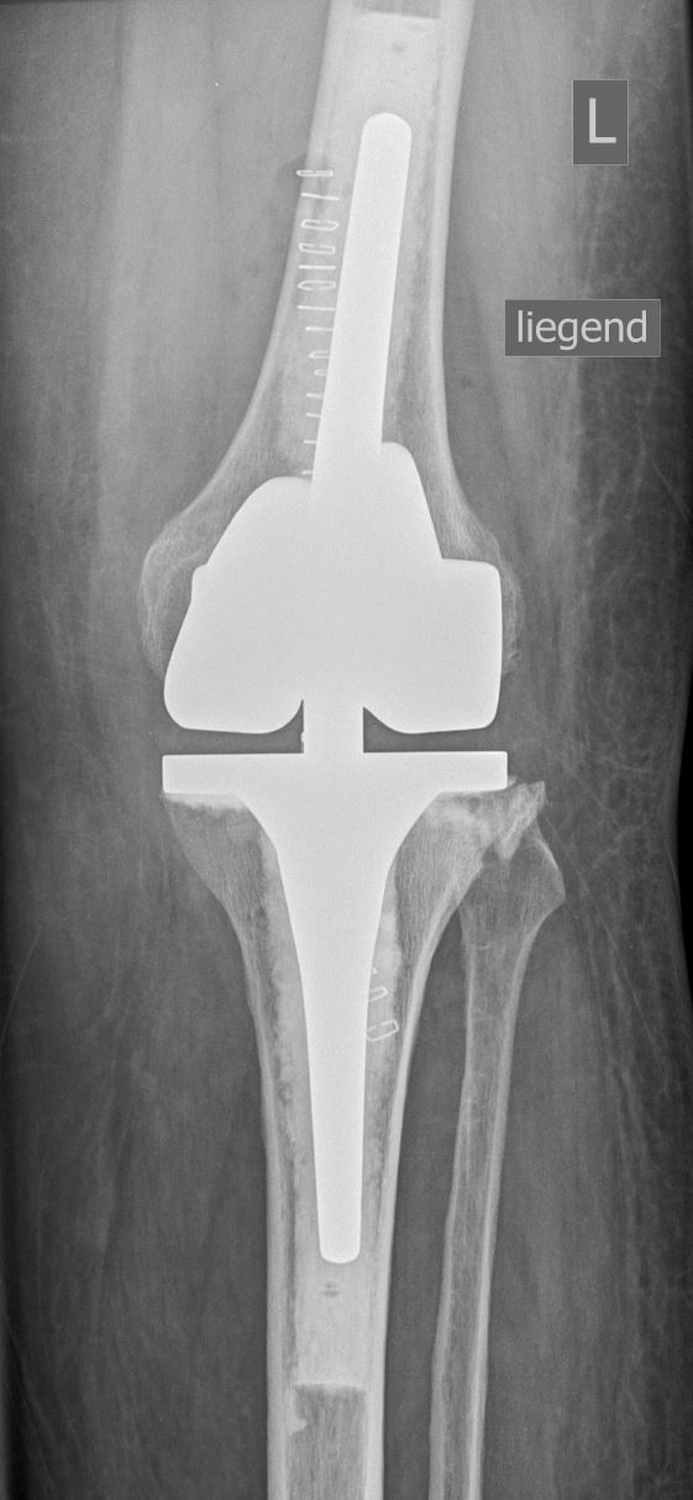

Bei der Implantation einer Knieprothese werden die zerstörten Gelenkflächen des Oberschenkel- und Schienbeinknochens millimetergenau entfernt und durch passgenaue Metallkomponenten ersetzt.

Dazwischen liegt ein hochbelastbares Kunststoffinlay, das die Gleitfläche bildet.

Bei der Implantation einer Knieprothese werden die zerstörten Gelenkflächen des Oberschenkel- und Schienbeinknochens millimetergenau entfernt und durch passgenaue Metallkomponenten ersetzt. Dazwischen liegt ein hochbelastbares Kunststoffinlay, dass die Gleitfläche bildet.

Je nach Schädigung und Gelenkzustand werden unterschiedliche Prothesenarten verwendet: